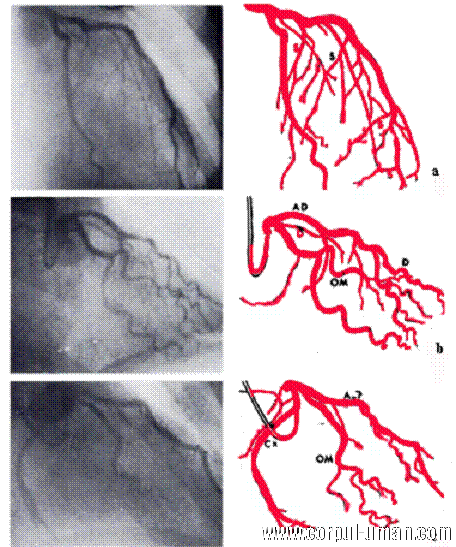

In acest punct, arterele coronare se desprind de obicei din aorta, iar cateterul este ghidat prin artera coronara dreapta sau stanga. Este injectata o substanta de contrast si, astfel, artera poate fi vizualizata cu ajutorul unor radiografii facute in planuri diferite.

Razele X vor arata inima si arterele, cele normale sau cele care sunt blocate de placi de aterom. Orice blocaj al arterei coronare este vizualizat foarte clar. Arteriografia coronara este o procedura relativ sigura in maini experimentate si atunci cand este realizata in laboratoare bine echipate. Mortalitatea este sub 0,05% iar complicatiile minore sunt rare.